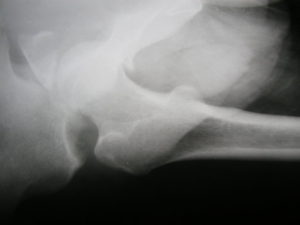

На рентгенограмме обнаруживаются следующие нарушения:

- Клиновидная деформация позвонка,

- Деформация передней поверхности тела позвонка,

- Увеличение межпозвонкового пространства,

- Смещение заднего отдела позвонка в позвоночный канал,

- Подвывих в межпозвоночных суставах.

В первую очередь выполняется рентгенографическое исследование поясничного отдела, причем проводится оно сразу в двух проекциях. Оно дает возможность обнаружить повреждения костной ткани позвонка.